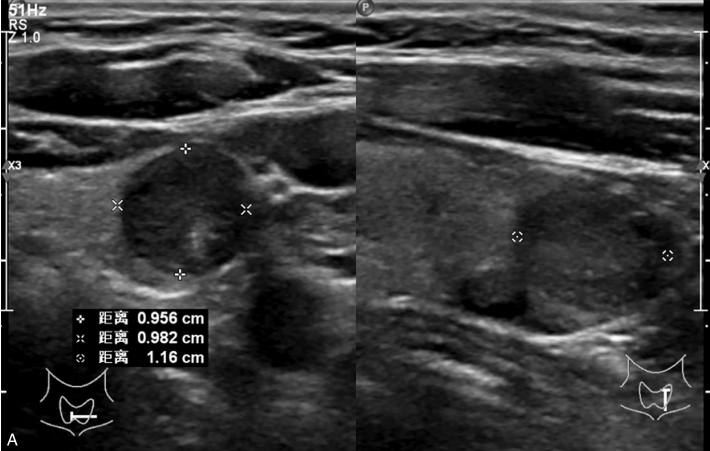

女性,56岁,体检超声发现甲状腺结节1周,无不适。甲状腺功能正常,实验室检查:FT3 3.76pmol/L,FT4 11.68pmol/L,TSH 2.8414μIU/ml。手术病理提示结节性甲状腺肿。

甲状腺形态基本正常,甲状腺实质回声稍增粗,分布尚均匀,甲状腺包膜尚光滑。甲状腺两叶内见多发结节,较大者位于左叶上极,呈类椭圆形,边界清楚,形态规则,纵横比<1,内部回声均匀,未见钙化,后方回声稍增强。CDFI显示左叶较大结节边缘可见丰富的条状血流信号,内部可见条状、点状血流信号,见图1-3-7。

图1-3-7 结节性甲状腺肿常规超声表现

A.常规超声图像;B.CDFI超声图像

甲状腺左叶上极较大结节增强早期呈稍高增强,自结节外周向中央灌注,增强晚期呈等增强,结节内部可见不均匀低增强区,见图1-3-8、ER1-3-4。

图1-3-8 结节性甲状腺肿超声造影图像

男性,64岁,体检发现甲状腺结节1天。体格检查:甲状腺无明显肿大。

甲状腺左叶中部实性中等回声,边缘光整,纵横比<1,内未见明显强回声,CDFI:结节内见血流信号,见图1-3-9。

图1-3-9 结节性甲状腺肿常规超声声像图

A.甲状腺左叶纵切面;B.CDFI血流图

甲状腺左叶中部结节15s开始增强。增强早期与周围正常甲状腺组织呈同步等增强,内部增强不均匀,增强后结节边界清,形态规则,周边可见环状高增强,增强晚期呈不均匀性低增强,见图1-3-10、ER1-3-5。

结节性甲状腺肿超声造影表现为病变多与周围正常甲状腺组织呈同步等或高增强,增强多较均匀,伴有囊性变者,内部可见无增强区,增强后结节边界清,周边可见环状增强,增强晚期呈等或稍高增强,也可呈稍低增强。

图1-3-10 结节性甲状腺肿超声造影图

A.增强早期结节呈同步不均匀性等增强;B.增强晚期呈不均匀性低增强